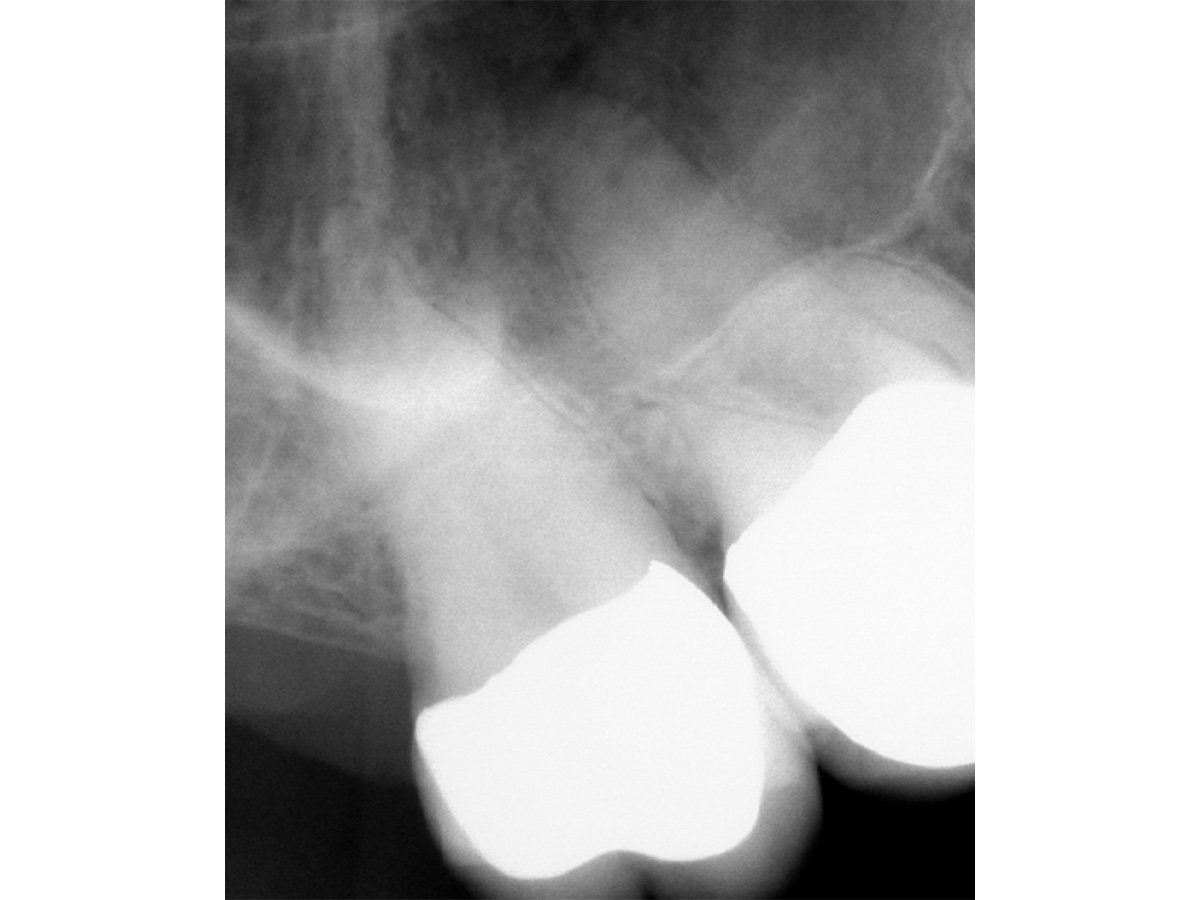

Abbildung 1

Röntgenologisch (Einzelbild 16-17) sind zwei Einzelkronen erkennbar. Keine zusätzliche diagnostische Information.